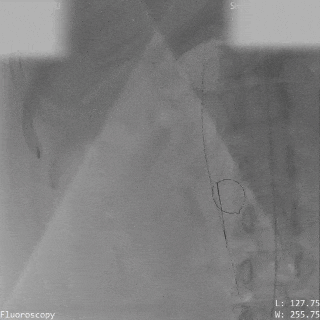

导丝通过主动脉窦瘤破口(左);导丝置于下腔静脉(右)

圈套器抓取导丝建立完整轨道